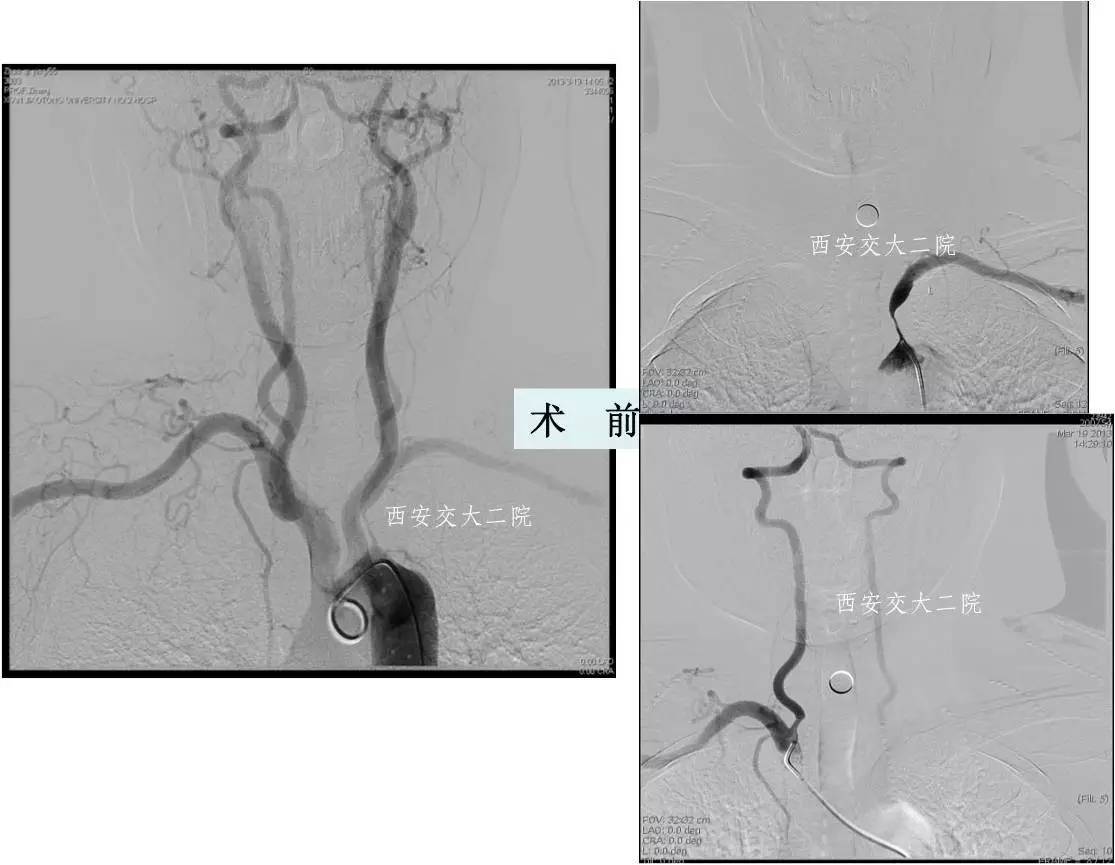

Case 1 基底动脉取栓 (2013年)

》35岁,女性;

》剖宫产后4天,右侧肢体活动不灵,言语不清13小时入我科。入科后3小时病情逐渐加重。

》术前查体:吸气困难,可见三凹征,指脉氧97%,心率60次/分,血压120/70mmHg. 意识清醒,不能言语,理解力正常,双侧瞳孔正常,眼球运动正常,双侧闭眼不紧,不能张口,流涎,不能伸舌,四肢肌力0级,双上肢肌张力低,双下肢肌张力高,双侧巴氏征阳性。

术前DSA

术后DSA